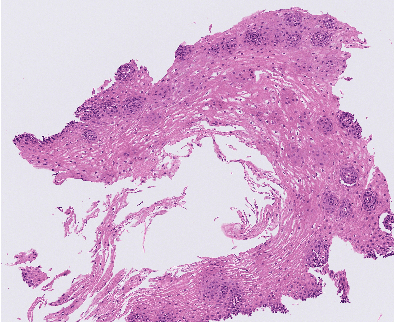

Abstract:Eosinophilic Esophagitis (EoE) is an allergic condition increasing in prevalence. To diagnose EoE, pathologists must find 15 or more eosinophils within a single high-power field (400X magnification). Determining whether or not a patient has EoE can be an arduous process and any medical imaging approaches used to assist diagnosis must consider both efficiency and precision. We propose an improvement of Adorno et al's approach for quantifying eosinphils using deep image segmentation. Our new approach leverages Monte Carlo Dropout, a common approach in deep learning to reduce overfitting, to provide uncertainty quantification on current deep learning models. The uncertainty can be visualized in an output image to evaluate model performance, provide insight to how deep learning algorithms function, and assist pathologists in identifying eosinophils.